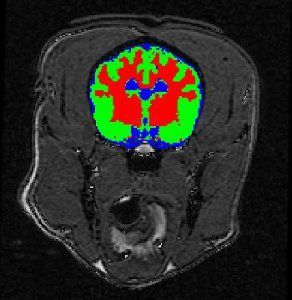

We are able to co-register images to enable low resolution quantitative images to be co-located with high resolution anatomical mages to allow accurate regions of interest to be drawn of the low resolution images. Brain images can be segmented into grey matter, white matter and cerebrospinal fluid. Regional blood flow and blood volume can be determined using either an MRI or a CT acquisition. Time activity curves can be generated from nuclear medicine studies to determine first pass kinetics.